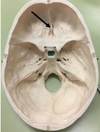

1. Identify the elevation. 2. What is the function of this structure?

1. Frontal Crest and Crista Galli 2. Attachment of Falx Cerebri, olfactory bulbs run lateral to it.

105

1. Foramen caecum 2. it transmits the emissary vein from the nose to the superior sagittal sinus. This has clinical importance in that infections of the nose and nearby areas can be transmitted to the meninges and brain from what is known as the danger triangle of the face.

106

1. Identify the elevation. 2. What is the function of this structure? 3. What structures are immediately lateral to this elevation? 4. This structure is perforated by what structures?

1. Crista Galli 2. Attachment of falx cerebri 3. Olfactory bulbs 4. Olfactory nerve rootlets

107

1. Identify the depression. 2. What structure is traversed through this depression if it is patent? 3. The structure identified in 2. connects which two areas? 4. When this structure is clinical significance if this structure is patent?

1. Foramen caecum 2. Emissary veins 3. Nose to superior saggital sinus 4. Infection can spread; meningitis